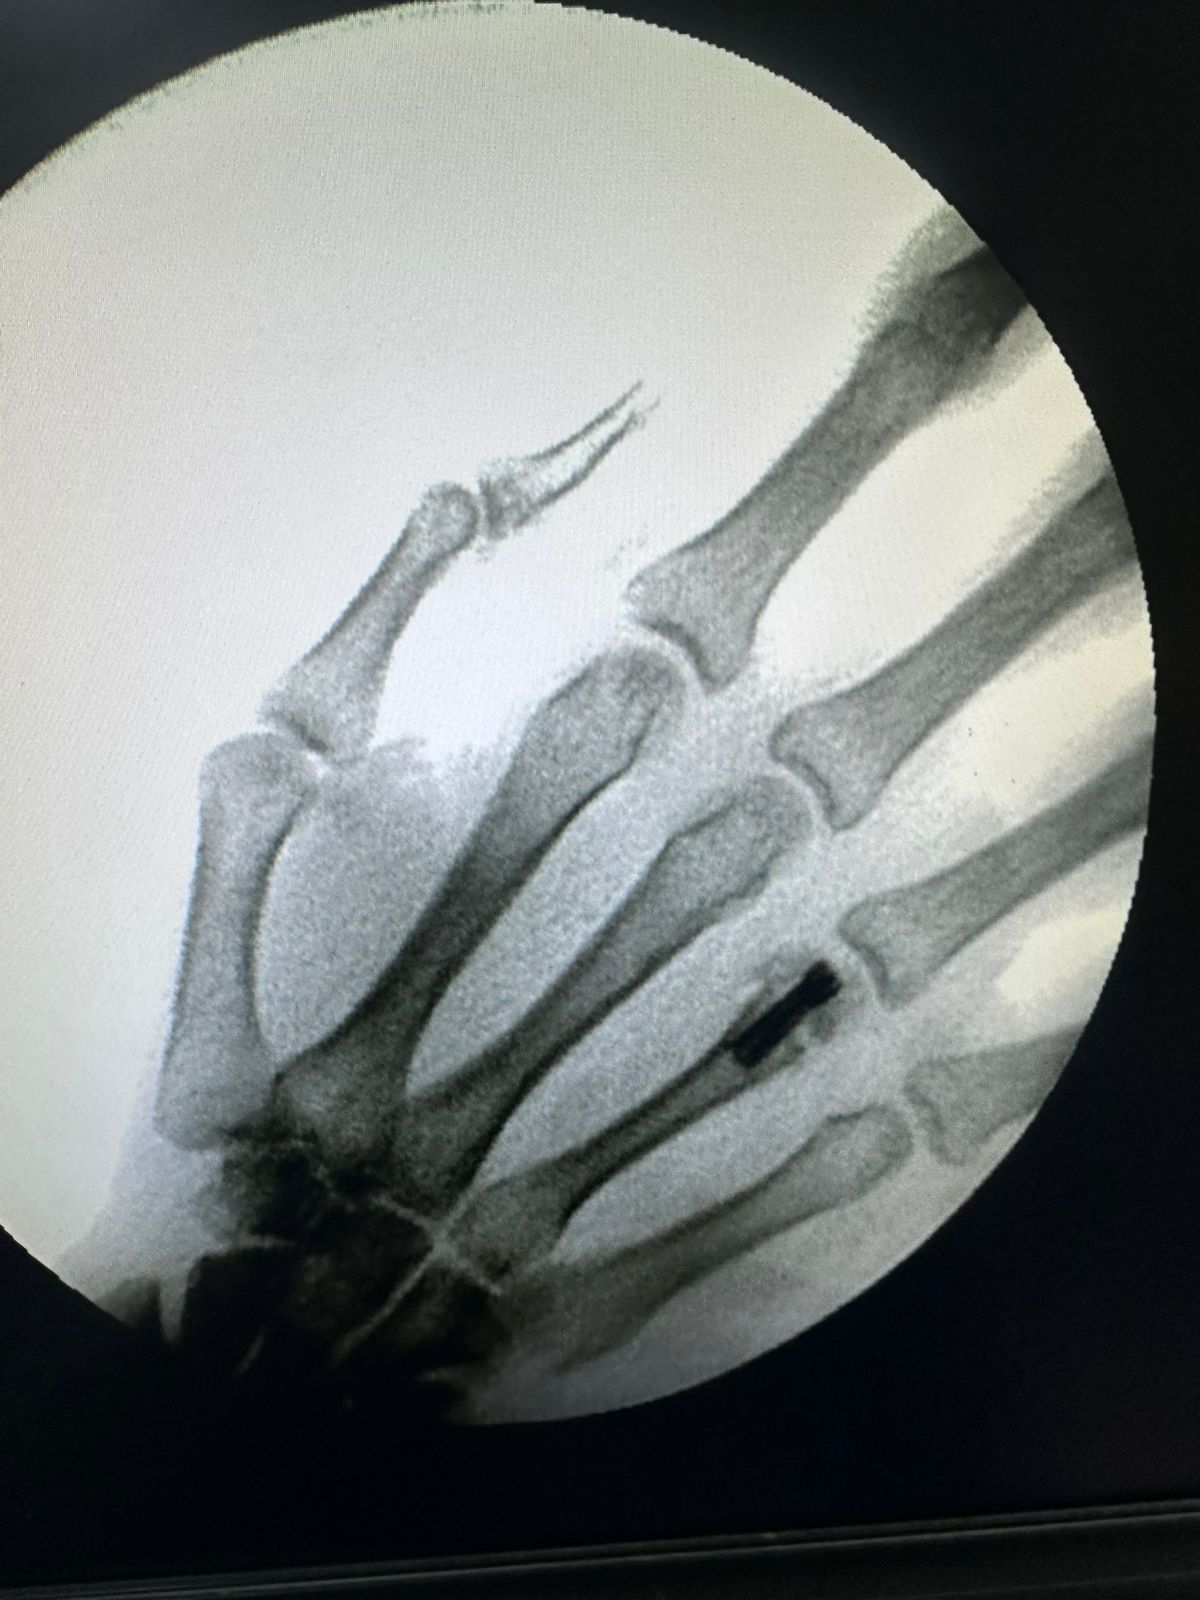

Moments That Mark Meaningful Recovery

Witness real patient transformations at The Ortho Clinic through images that reflect successful treatments and restored mobility.